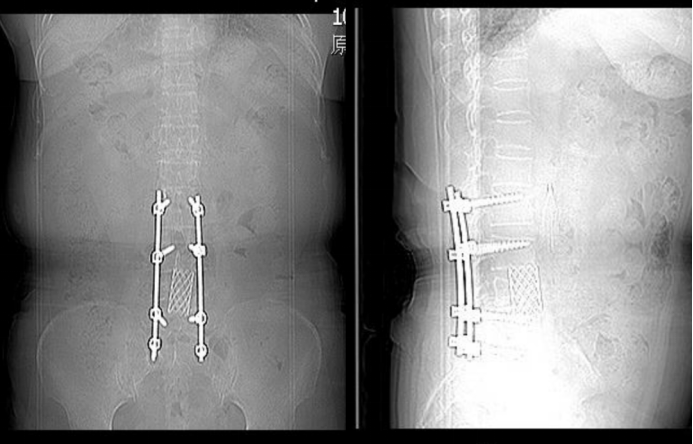

Surgical Treatment: Spinal fusion from L2 to S1, comprising lumbar laminectomy (for decompression), discectomy, interbody cage placement, and bone grafting fusion. Instrumentation involved posterior fixation using a 4.75 system with 10 screws and 2 rods, along with cage(s).

Postoperative imaging